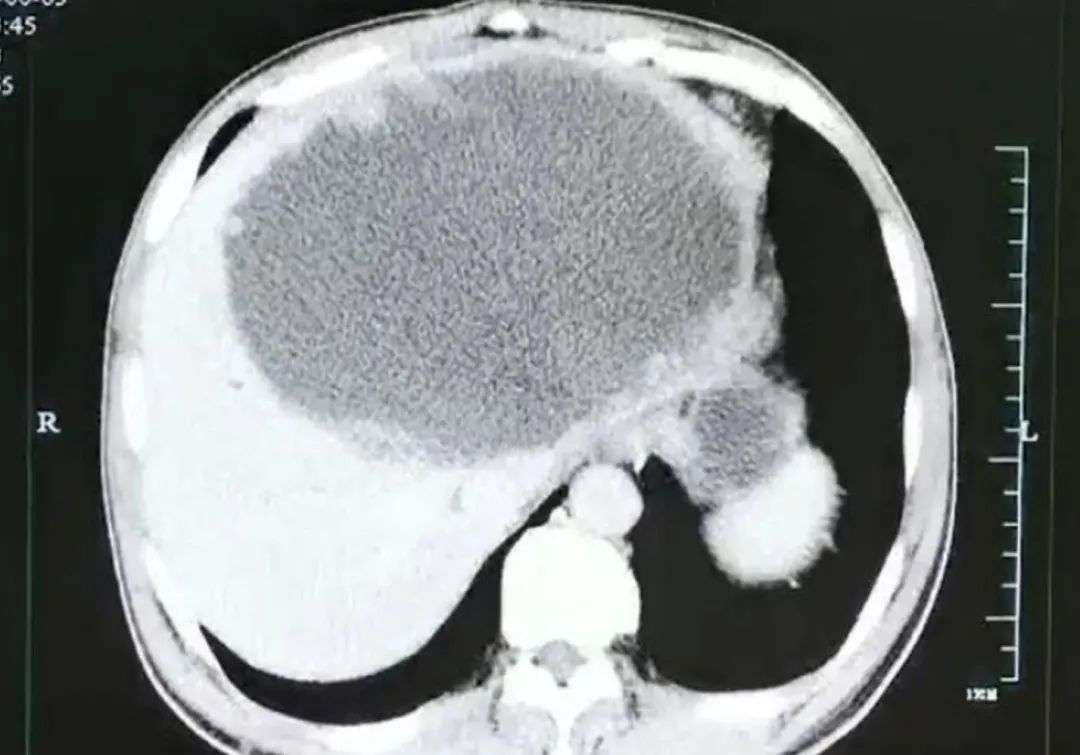

下图,2021年典型案例,四川谢先生在食用生鱼后,入院查出左肝被掏空。

罪魁祸首,就是肝吸虫。